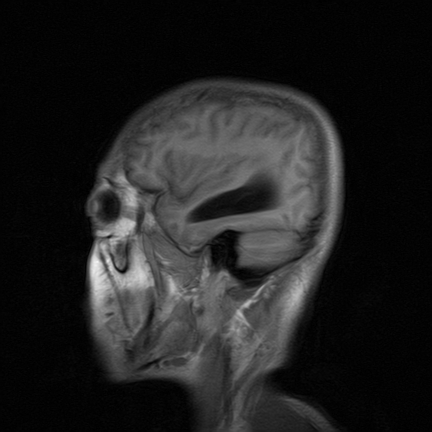

标题: MRI2064:少见病例。男性52,视力下降多年。 [打印本页]

标题: MRI2064:少见病例。男性52,视力下降多年。

四脑室区见混杂信号占位影,脑室系统扩张明显,临近结构显著受压称位,患者52岁,多考虑室管膜瘤可能性大

应该是来源于小脑蚓部的占位,如血管母细瘤或星形细胞瘤

考虑第四脑室室管膜瘤并梗阻性脑积水;部分性空蝶鞍;左侧上颌窦粘膜下囊肿。

小脑蚓部胶质脑膜瘤突入四脑室;肿瘤内见血管流空信号和钙化信号.

比较典型的脉络丛乳头状瘤并脑积水,鉴别小脑蚓部血管母细胞瘤。